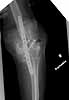

My fixation failed in January 2004. Please see attached files (first revision fail).

1st revision fail